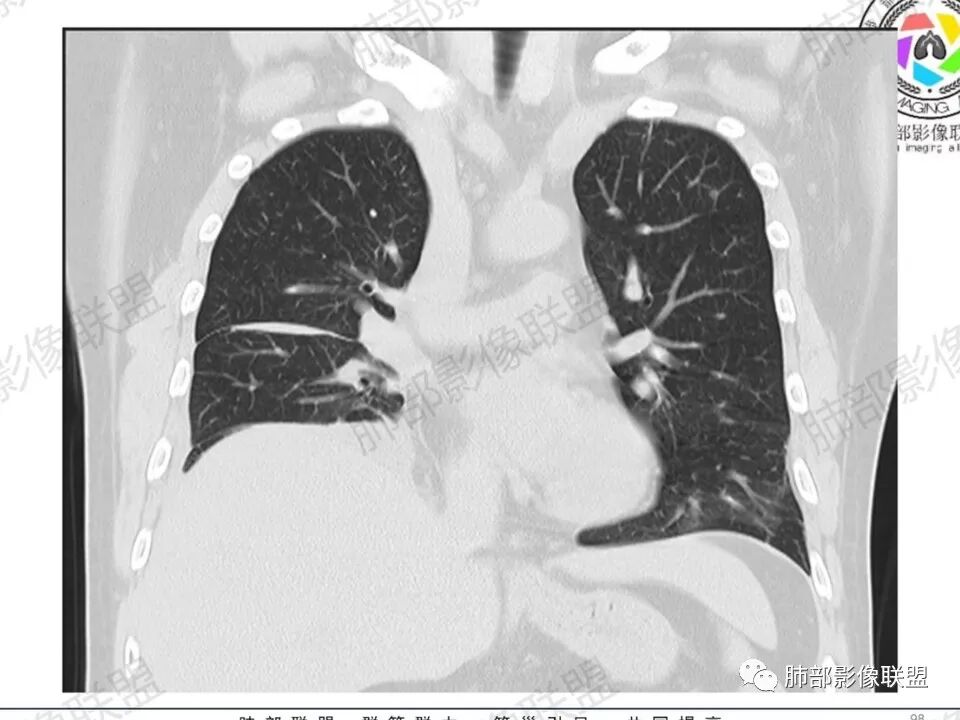

双肺多发结节,胸膜下为主,部分可见空洞。左肺上叶尖后段结节较大,分叶毛刺,周围可见长条索及小斑片影,内空洞比较光滑,内侧壁可见支气管通过。右肺下叶后基底段不张实变,后侧积液,右侧水平裂积液,右侧膈胸膜纵膈胸膜增厚积液,右侧侧胸膜肥厚,考虑1:一元金葡。2二元:金葡,左肺上叶结核。

感觉还是金葡入血形成SPE可能性较大,胸水+楔形影+胸膜结节

中年男性,左手中指及胸壁疼痛伴发热来诊,影像见双肺多发结节,胸膜下分布为主,部分结节可见空洞,边缘模糊。左肺上叶尖后段结节较大。右肺下叶后基底段不张实变,右侧叶间裂及右侧胸腔积液,右侧侧胸膜肥厚。考虑金葡菌感染,血播SPE。

胸膜下为主多发结节,边缘光滑

伴随楔形影,支气管壁不增厚